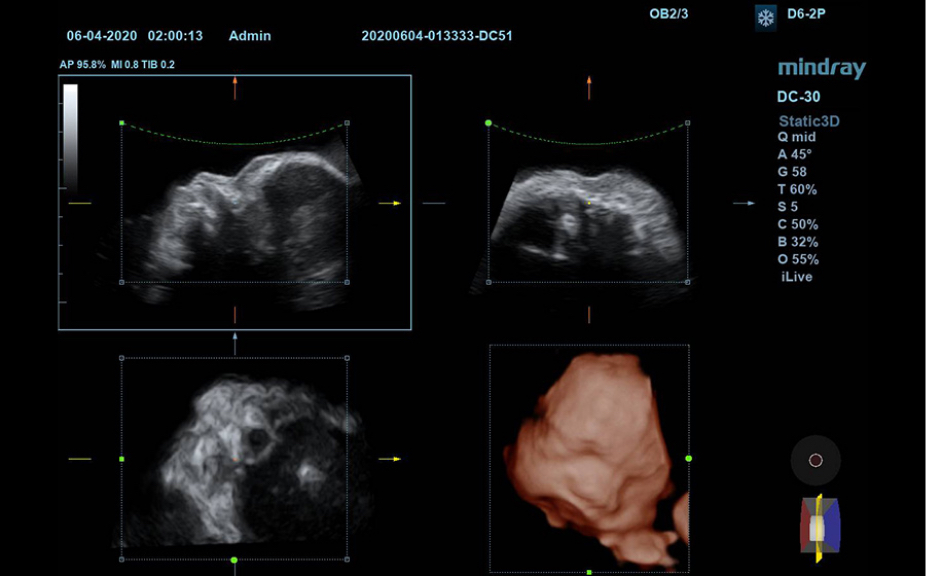

Ilustraciones anatĂłmicas normales que incluyen imĂĄgenes esquemĂĄticas y ecogrĂĄficas.

VisualizaciĂłn lateral de ultrasonografĂas estĂĄndares que proporciona orientaciĂłn visual sobre la regiĂłn de interĂ©s.

ImĂĄgenes de ecografĂas estĂĄndares

3

ComparaciĂłn de ecografĂas en tiempo real para su referencia.

ImĂĄgenes de ecografĂas de referencia

ImĂĄgenes clĂnicas